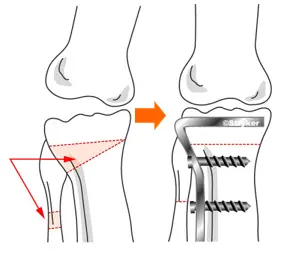

高位脛骨骨切り術(HTO)

脛の骨を切ってプレート・スクリューで固定し、O脚を矯正する手術です。

対象は変形が関節の内側のみの方に限られますが、自分の骨を残すことができ、比較的若年の活動度が高い方によい適応があります。スポーツに復帰される方もいます。